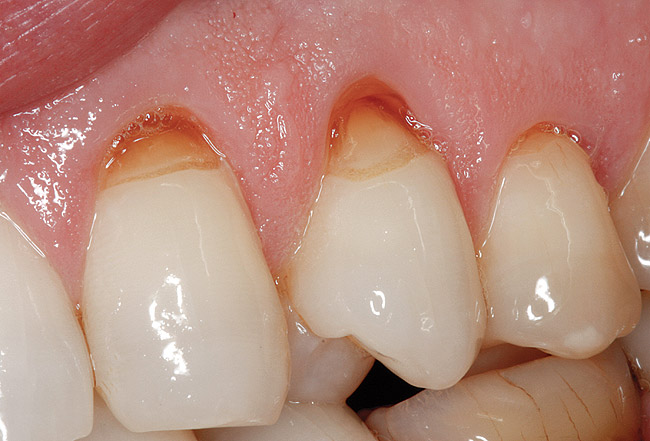

Figure  3  Severe dental erosion and attrition in a GERD patient.

Figure 3

Figure  6  Erosion and abrasion in a xerostomic patient with Sjögren’s syndrome.

Figure 6